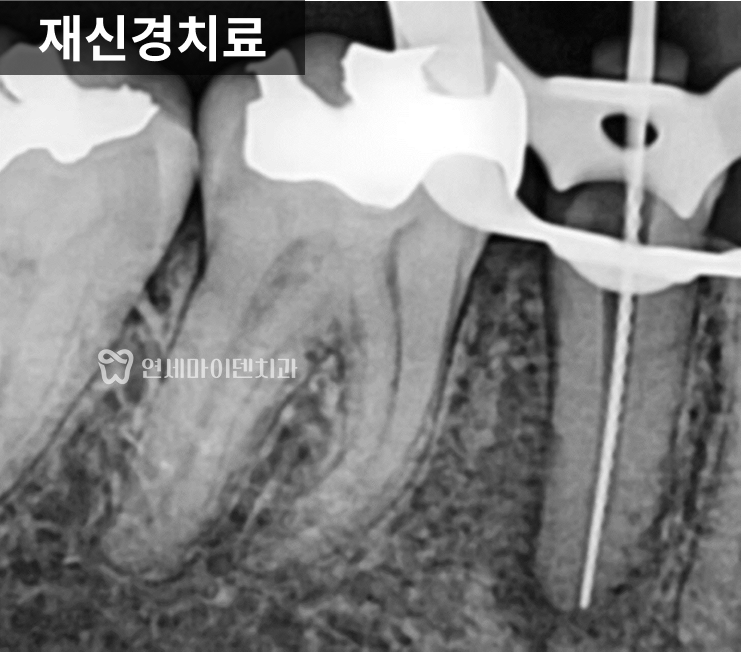

근본적인 치료, 재신경치료 및 회복 과정

치아를 살리기 위해

선택한 방법은 재신경치료였습니다.

미세현미경을 이용해 이전 신경치료에선

닿지 않았던 뿌리 끝까지 깨끗하게 소독하고,

내부를 철저히 청소한 뒤 밀폐했습니다.

치료 후에는 항생제도 쓰지 않았고,

고름을 억지로 짜낸 적도 없었습니다.

그저 내부 감염을 확실하게 제거하고

몸이 스스로 치유할 시간을 주었습니다.

불과 2~3주 만에 잇몸 여드름은 사라졌고,

몇 달 뒤에는 뼈가 다시 차오르면서

치아를 정상적으로 사용할 수 있었습니다.